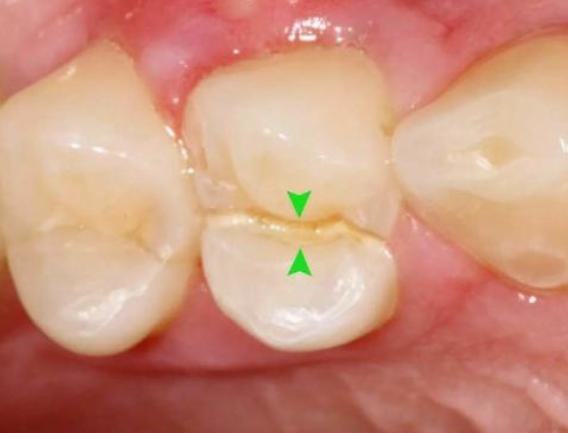

于是抱着侥幸心理,让牙齿在没有“防护衣”的情况下:咬着小坚果,嗑着小瓜子……有一天,“咔”!牙齿劈裂了!

根管治疗是针对牙髓炎或牙髓坏死、根尖病变不能保留活髓的折裂牙,进行治疗的有效方法。

- 牙髓裸露:当牙齿折断并且牙齿的神经暴露时,通常需要进行根管治疗。